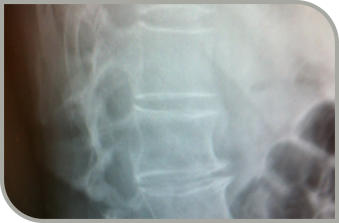

2008 Röntgenbilder lesen Bodyfeet Aarau